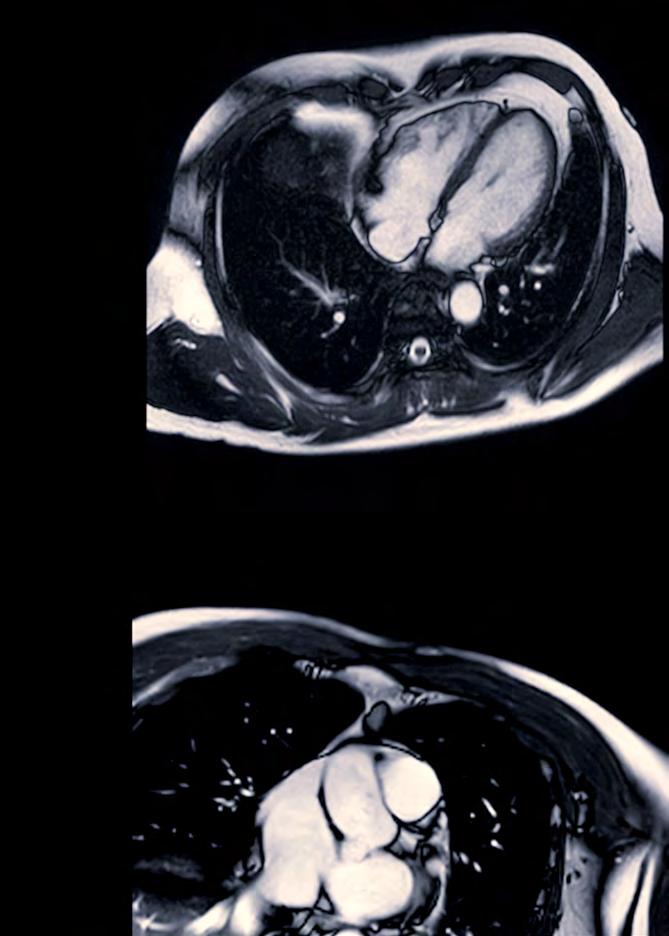

David Nordsletten, U-M Professor, Biomedical Engineering and Cardiac Surgery, along with Ralph Sinkus, INSERM and King’s College London, Chair and Professor, Biomedical Engineering and Research Director of CNRS/France, Paris, present a novel scattering theory, in conjunction with MRI-based elastography imaging, which enables the unraveling of a material’s innate constitutive and scattering characteristics. By overcoming a three-order-of-magnitude scale difference between wavelength and average inter-vessel distance, they demonstrate non-invasively a macroscopic measure of vascular architecture.

Drs. Nordsletten and Sinkus explained that researchers can see waves inside an object using similar wave technology. The technology is based on seeing waves inside the object via MRI, where external vibrations are transmitted through the

body to show their spatial organization as they traverse organs and tissues. From these waves, it is possible to analyze the physics.

Cardiac MRI images are instrumental in assessing cardiac health, identifying heart abnormalities, and guiding treatment plans.

- David Nordsletten, Professor, Biomedical Engineering and Cardiac Surgery